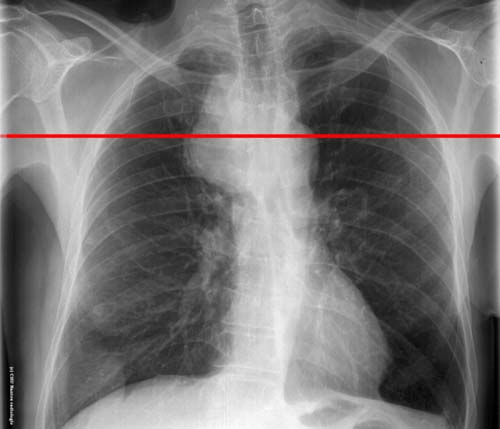

Syndrome médiastinal : niveau de la coupe TDM